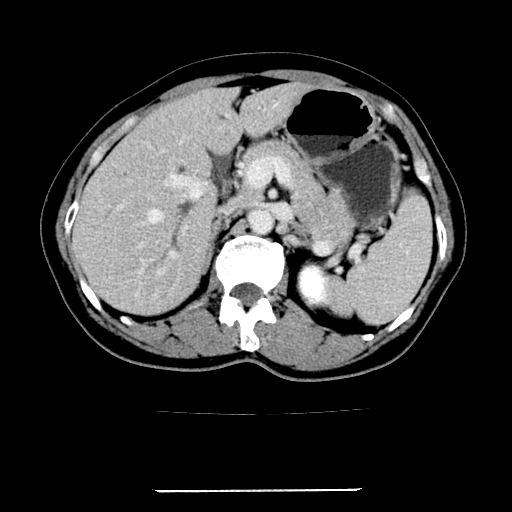

女,67岁,上腹部疼痛一周伴皮肤黄染,无发热。

左叶肝内胆管结石,并远端肝内胆管扩张。

考虑:肝内胆管结石继发肝内胆管扩张,右肾旋转不良。

肝内外胆管结石并肝内胆管扩张。

1、肝门高密度影下层面和胰头层面可见轻度胆管扩张,而静脉和延迟期均未见扫描完胰头,不能完全排除胰头占位。2、肝门部高密度影,考虑钙化或结石。

考虑肝门胆管癌伴门脉左支受侵包埋,建议mrcp进一步检查。